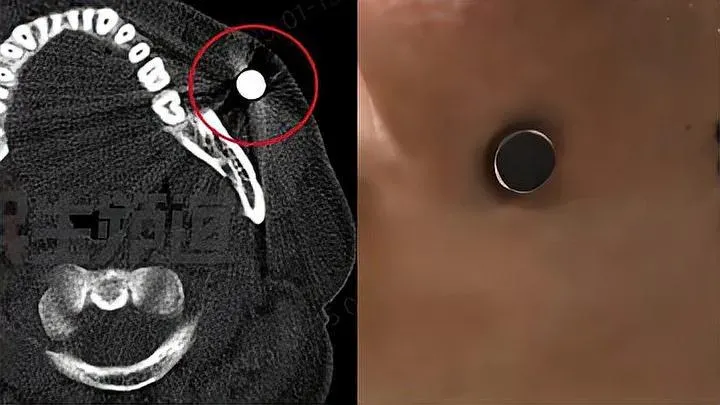

男子面部紅腫到可以吸住磁鐵,原因是藏了小鋼珠。(小莉幫忙)

真有「磁力王」?河南鄭州一名男子日前赴醫院求醫,稱面頰受傷後不僅腫了4天,還能「吸住磁鐵」,讓接診醫生驚呼20年來頭一次見到,經檢查發現,原來是藏了一顆「小鋼珠」。

經趙媛仔細詢問,李先生這才緩緩道出受傷經過,原來前幾天和幾個鄰居老人一起玩彈弓,由於自己不太會使用,當時繩子彈到臉上了,以為是割傷過兩日就能康復,卻沒想到臉越腫越大,直到家人提醒「不會是鋼珠打到裡面了吧」,他急忙拿個磁鐵測試,果然「黏住了,這下糟了」,遂急忙赴醫院。

面部傷口化膿 幸及時處理

經過手術治療,醫生趙媛從李先生面部取出一顆完整帶有鐵銹的鋼珠,順著鋼珠還流出膿性液體,研判已感染化膿,幸好及時處理,傷口才未進一步惡化,若鋼珠遲遲未取出,恐引發面部感染,嚴重會導致面部腫脹疼痛,甚至張口受限,呼吸吞嚥困難。